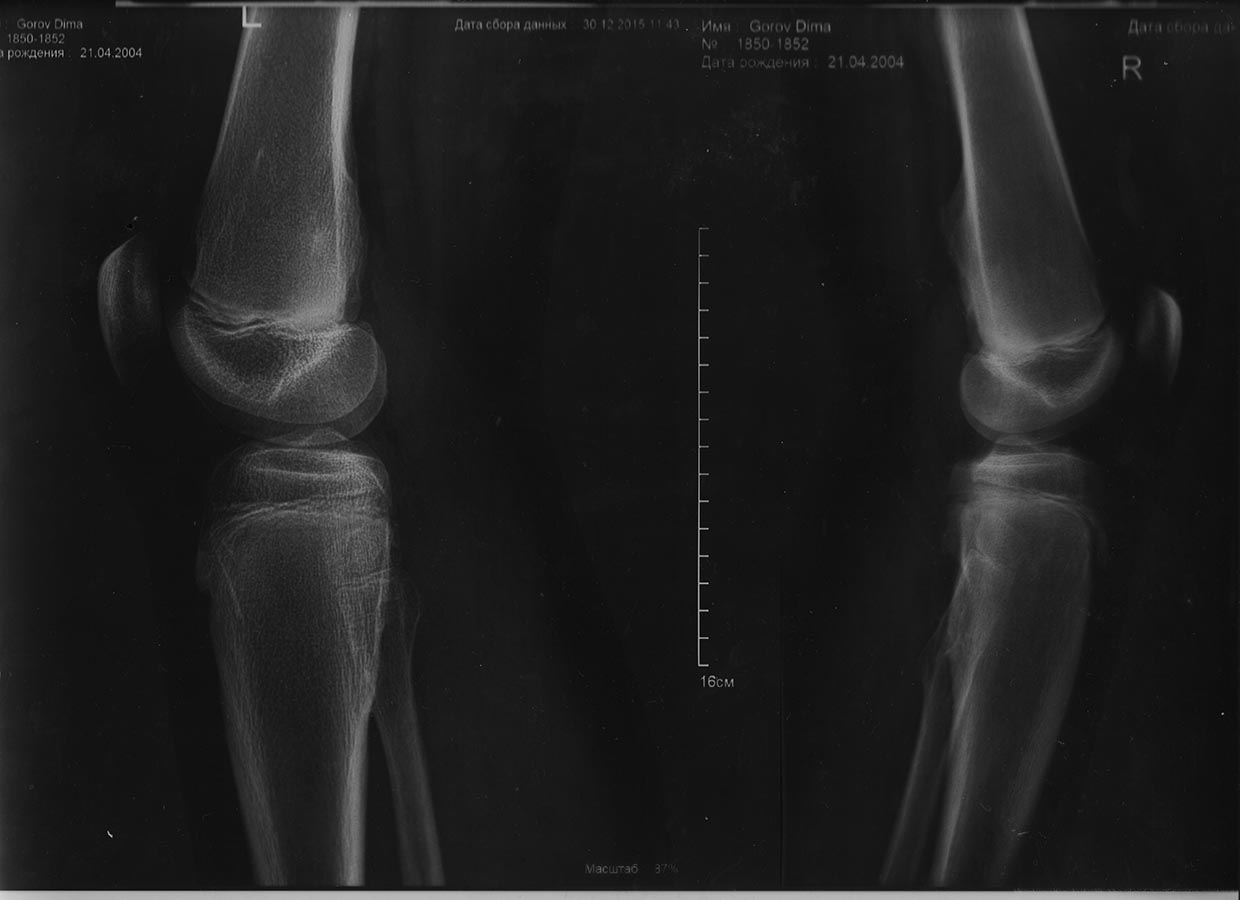

Ко мне обратился ребёнок 11 лет с жалобами на боли в области коленных

суставов, рентген прилагается. Кто как лечит данную патологию, в каких

случаях прибегаете к операции. Заранее

спасибо за ответ.